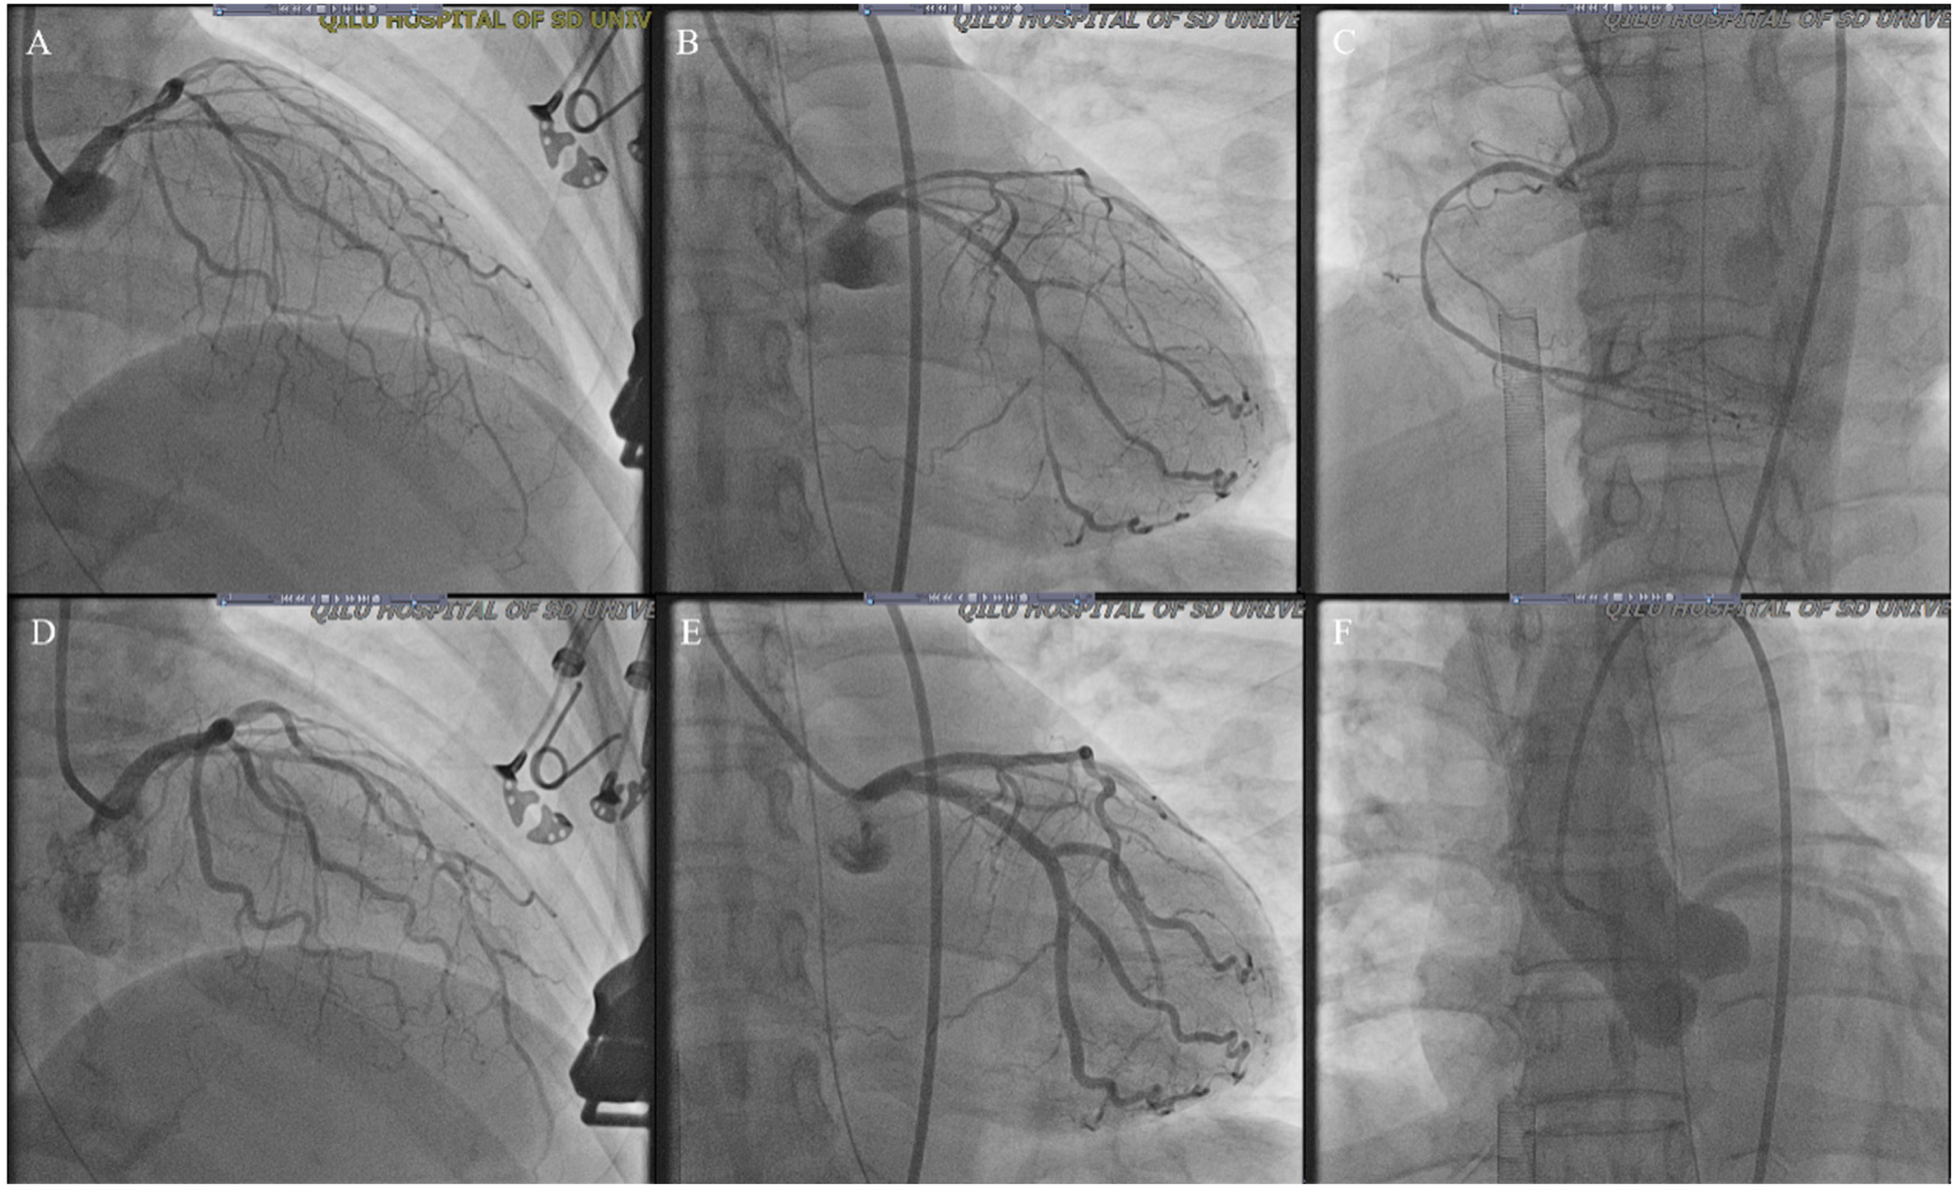

Figure 3

Coronary angiogram from the current stay. (A–C) Diffuse slender of LAD, LCX and RCA (D,E) improved LAD and LCX spasm after intracoronary injection of 100 ug nitroglycerine; (F) showed normal ascending aortography (LAD, left anterior descending artery; LCX, left circumflex artery; RCA, right coronary artery).

A 52-year-old female was admitted to the emergency room because of sudden chest pain and chest tightness, with a history of hypertension, coronary heart disease and abnormal uterine bleeding for 20 days. She had multiple previous episodes of chest distress and chest pain after activity that coronary computed tomography angiography showed coronary atherosclerosis. The patient had history of taking aspirin, isosorbide mononitrate sustained-release tablets, atorvastatin, isosorbide mononitrate sustained-release tablets, and stopped aspirin for 1 week because of abnormal uterine bleeding. There's no history of smoking, drug abuse or unprescribed medications. The patient went to the gynecology outpatient service 1 day before the disease's onset. Laboratory examination revealed beta-human chorionic gonadotropin (β-HCG), 0 mIU/ml, and hemoglobin, 70 g/L. Ultrasound revealed multiple myomas of the uterus and uneven thickening of the endometrium. Iron polysaccharide complex capsules were given to correct anemia. Echocardiography was performed 2 days prior, and the left ventricular ejection fraction was 72%. The patient repeatedly experienced chest pain and discomfort at 1 a.m., accompanied by chest tightness and sweating. When she entered the emergency room at 9 a.m., her vital signs were as follows: blood pressure of 128/96 mmHg (right arm, supine position), heart rate of 99 bpm, respiratory rate of 15/min, oxygen saturation of 99% and temperature of 36.6°C. Her cardiac troponin level was totally normal. ECG revealed T wave changes in leads V2, V3, V4, and V5 (Figure 1). Vital sign monitoring, nasal catheter oxygen inhalation (3 L/min), and coronary vasodilator (nicorandil 12 mg intravenous drip) were performed. Considering the AUB, antiplatelet drugs were not given at the first time. Cardiology experts recommend a short-term reexamination of ECG and cardiac troponin to assess the indications for early coronary angiography. The patient's symptoms of chest pain were relieved after treatments. The patient's chest pain reappeared at noon and could not be relieved continuously. During the reexamination of the ECG, the patient suddenly experienced loss of consciousness, sweating, and a decreased heart rate. ECG revealed ST-segment elevation in leads II, III and the AVF which limb leads is type 1 s-degree atrioventricular block (Wenckebach) and chest leads is 2:1 s-degree atrioventricular block (Figure 2). The troponin level was 0.016 ng/ml, which was considered acute myocardial infarction. She was given a loading dose of aspirin 300 mg and clopidogrel 300 mg orally according to the cardiology consultation. Bedside ultrasound revealed that left ventricular systolic function decreased diffusely to less than 10%, and the femoral artery was untouched. Endotracheal intubation, isoproterenol, and norepinephrine were given immediately. After that, the patient underwent episodes of cardiac arrest with pulseless electrical activity, and ECPR was started after traditional cardiopulmonary resuscitation. The ICU team placed VA-ECMO beside the bed to restore spontaneous circulation. The vital signs were as follows: blood pressure of 117/95 mmHg (right arm, supine position, 0.4 µg/kg/min norepinephrine), heart rate of 131 bpm, controlled ventilation at 14/min, and a temperature of 36.1°C. The initial setting parameters of ECMO were as follows: rotation speed of 2,780 r, flow rate of 3.63 L/min, gas flow rate of 3 L/min, oxygen concentration of 50%, and water tank temperature of 36°C. The blood gas analysis showed that the patient's hemoglobin had dropped to 49 g/L at 3:40 p.m. and we gave blood transfusion immediately at 4 p.m. The patient underwent urgent coronary angiography. Figure 3 revealed a diffuse slenderness of the coronary artery and severe narrowing of the left circumflex (LCX) arteries, in which the heaviest stenosis was 90%. Suspecting spasm, the left coronary artery was injected intracoronary with 100 µg nitroglycerine, which completely relieved the spasm. After relief of spasm, angiography showed left anterior descending artery (LAD) had atherosclerosis with no significant stenosis or occluding lesions, which in good blood flow. The inferior myocardial infarction was confirmed to be caused by coronary vasospasm, and the postoperative electrocardiogram (Figure 4) revealed that the ST segment returned to baseline. The cardiac troponin levels obtained 4 and 12 h later were 2.1 ng/ml and 2.2 ng/ml, respectively.